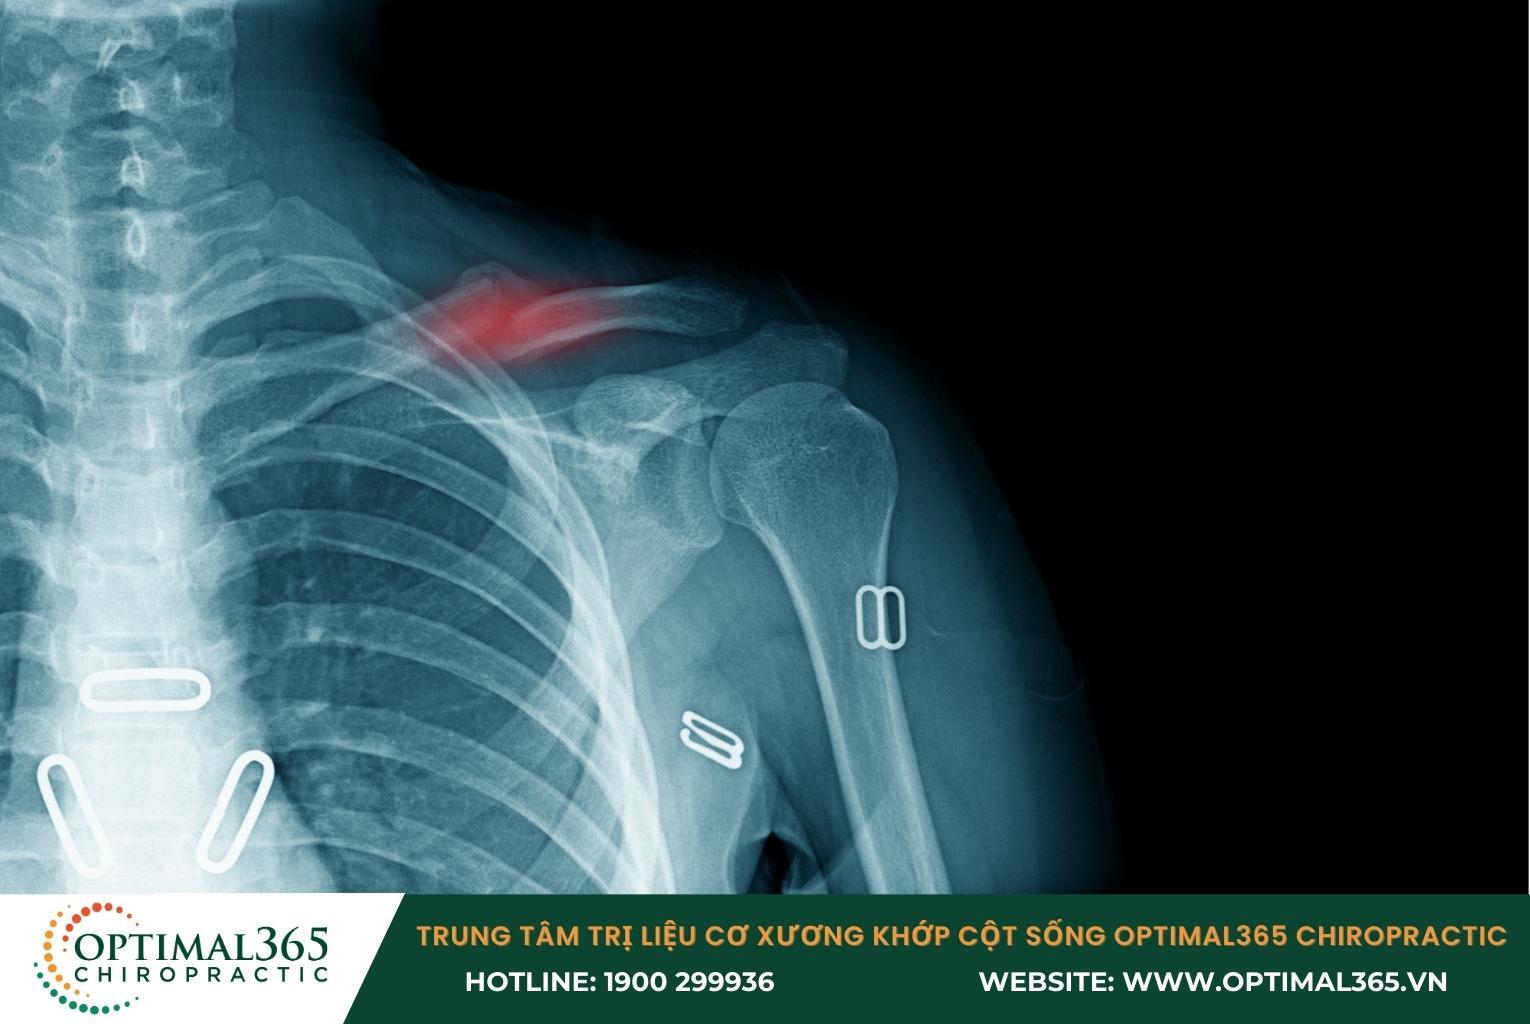

Gãy xương bả vai

Lực tác động mạnh do té ngã, tai nạn có thể làm xương bả vai bị rạn nứt hoặc gãy. Loại chấn thương vai này dễ xảy ra nhất ở phần đầu hoặc phần thân của xương cánh tay và xương đòn.

Các triệu chứng đặc trưng của tình trạng gãy xương bả vai là:

• Đau đớn tại vị trí gãy, cơn đau nhanh chóng lan tỏa khắp phần bả vai.

• Sưng to và bầm tím khu vực khớp vai.

• Khó khăn khi nhấc cánh tay lên, có tiếng động rắc rắc khi di chuyển khớp vai.

• Có thể nhìn thấy hoặc chạm thấy phần đầu xương nhô lên khỏi da.